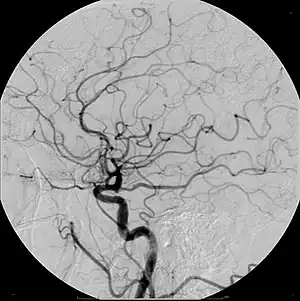

| Cerebral Angiogram obtained using an iodine based contrast medium | |

Due to positive remodeling the plaque build-up shown on angiogram may appear further downstream on the x-ray where the luminal diameter would look normal even though there is severe narrowing at the real site. Because angiograms require x-rays to be visualized the number of times an individual can have it done over a year is limited by the guidelines for the amount of radiation they can be exposed to in a one-year period.[2]